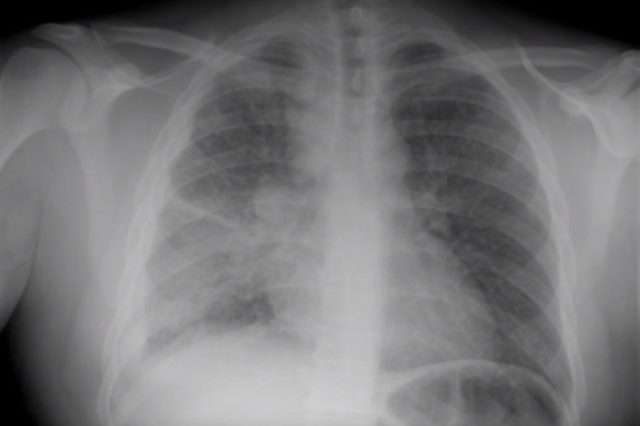

- рентгенологического исследования: при остром этапе заболевания в значительном количестве выявляются схожие на цепочки очаговые соединения; хроническая форма выражается ассиметричным размещением разных очаговых теней; диагностика подострого процесса характеризуется при сформировавшихся из объединившихся очагов каверн распада;

Диссеминированный туберкулёз лёгких – клиническая форма, характеризующаяся образованием множественных туберкулёзных очагов. Под этим названием было собрано несколько разнообразных по клиническим проявлениям заболеваний, объединённых наличием на рентгенограмме органов грудной клетки изменений симметричных в пространстве (двусторонние, приблизительно в аналогичных сегментах, чаще в верхних отделах) и во времени (изоморфность, одинаковая степень развития процесса – очаги, инфильтрация, каверны и т.п.).

Рентгенография. Если изначально лихорадка длится более 7-10 дней (что редко бывает при большинстве инфекций), то исключение милиарного туберкулёза необходимо. Чаще всего через 10-14 дней возникают изменения на рентгенограмме. Они изначально носят нежный характер, но достаточно быстро нарастают. Морфологическая основа рентгенологической картины – туберкулёзные очаги, образующиеся при слиянии туберкулёзных бугорков. Милиарный туберкулёз характеризуется наличием многочисленных мелкоочаговых теней, равномерно рассеянных во всех отделах лёгких. Очаги локализуются по ходу сосудов цепочками по 4-5 очагов. Как правило, они не превышают 2-3 мм в диаметре, за что их называют просовидными, или милиарными (от латинского milium – просо, просяное зерно).

Иногда создаётся впечатление, что в средних и нижних отделах очагов больше, но это – следствие большей толщины лёгкого в этих отделах и тесного прилежания именно средних и нижних участков к кассете при рентгенографии. Воспалительное уплотнение междольковой и внутридольковой лёгочной межуточной ткани приводит тому, что лёгочный рисунок приобретает мелкосетчатый и петлистый характер. Эксперты ВОЗ при подозрении на милиарный туберкулёз рекомендуют сделать более жёсткий снимок и смотреть его при ярком свете, обращая особое внимание на межрёберные пространства: в этом случае можно разглядеть первые небольшие очаги. Согласно данным североамериканских клиницистов, типичная рентгенологическая картина милиарного туберкулёза – двусторонняя симметричная тотальная мягко- и мелкоочаговая диссеминация, изначально распознаваемая на боковых снимках или на мягких рентгенограммах. Если больной не получает лечения, очаги сливаются, нарастает картина двусторонней инфильтрации, снежной бури. Такие рентгенологические изменения соответствуют обширному казеозу лёгочной ткани.

Достаточно информативно бактериологическое исследование мокроты на М. tuberculosis, особенно при наличии признаков распада лёгочной ткани. При поражении почек целесообразно провести посев мочи. Для рентгенологической картины подострого диссеминированного туберкулёза патогномонично поражение преимущественно верхних отделов, слияние очагов, наличие инфильтрации и формирование штампованных или очковых каверн, располагающихся довольно симметрично в верхних долях обоих лёгких. Увеличенные внутригрудные лимфатические узлы или наличие плеврита также будут свидетельствовать в пользу туберкулёзной этиологии диссеминации. Одновременно возможны экстраторакальные поражения.

Если больной измеряет температуру тела, то находят субфебрилитет. При деструкции лёгких довольно вероятно обнаружение микобактерий в мокроте. Иногда процесс выявляют при очередном профилактическом лучевом исследовании. Рентгенологическая картина хронического диссеминированного туберкулёза проявляется, прежде всего, симметричным поражением верхних отделов обоих лёгких, типично наличие полиморфных очагов, старых очагов, включая кальцинаты. Верхние доли со временем уменьшаются в объёме, подтягивая вверх корни лёгких. В нижних отделах развивается эмфизема.